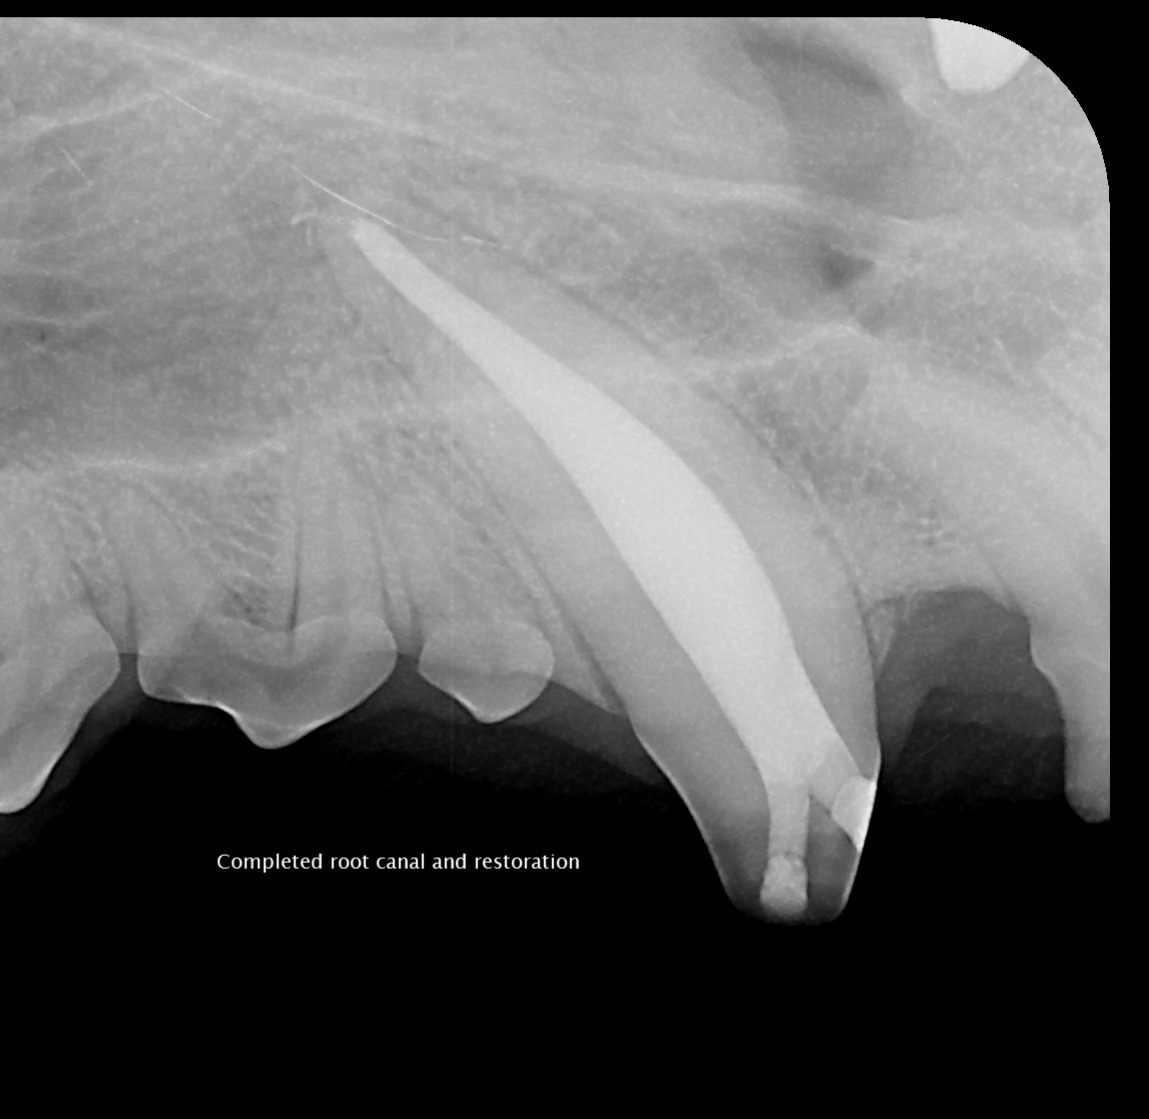

- Root canal therapy (endodontic treatment): We remove infected or dead pulp, thoroughly clean and seal the root canal system, and restore the tooth with a filling or crown. This is often the preferred choice for preserving important teeth and maintaining function.

Our team uses state-of-the-art diagnostics and gentle techniques to ensure your pet’s comfort throughout treatment. Before-and-after photos illustrate the clinical and radiographic results of a successful canine tooth root canal, showing how we can preserve and restore teeth to full function.